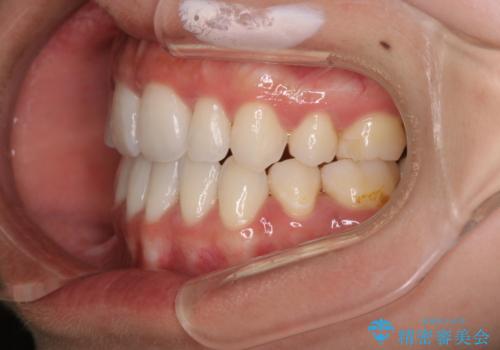

- 口元をさげたいという主訴で来院されました。4番の歯を4本抜歯し、遠心移動とIPRをしました。右上2番が矮小歯のため見た目を重視するならクラウンの提案をしましたが、そのままでの治療を希望されました。

矯正治療の最終段階でスペースクローズにやや時間がかかりましたが、前歯が下がったことで口元の位置も下がりきれいになりました。